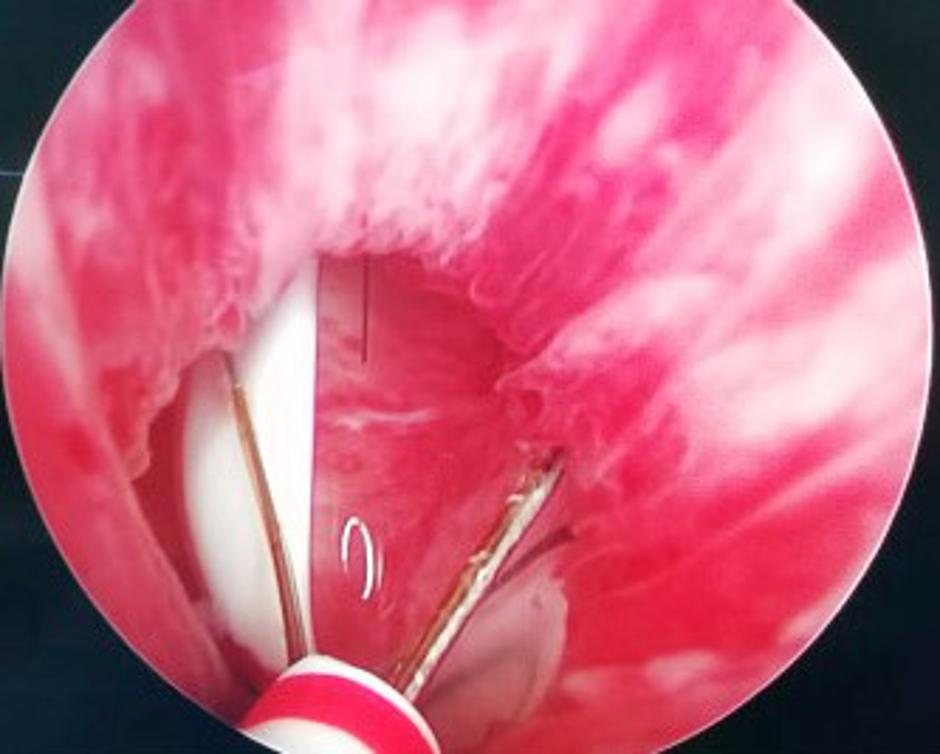

Čeprav je povedal, da mu je ob tem bilo prijetno, mu je bilo pozneje zagotovo žal. Čakala ga je namreč nadležna preiskava, da bi odkrili, kjer se tujek nahaja. Bolniku so opravili cistokopijo, kar pomeni, da so mu v sečnico vstavili cev s pritrjeno kamero. Ugotovili so, da je termometer že "prilezel" v mehur.

Urologi so termometer nato izvlekli, kar je trajalo 15 minut in bolnika naslednji dan že spustili iz bolnišnice, navaja Urology Case Reports, kjer urologi iz celega sveta poročajo o nenavadnih primerih - o bizarnih početjih ljudi, ki si s takšnimi ali drugačnimi spolnimi praksami ogrožajo življenje.

"V tem primeru smo morali biti zelo previdni pri odstranjevanju predmeta, saj bi se lahko termometer zlomil, kar bi povzročilo poškodbe sten mehurja," so zapisali zdravniki. Poleg tega je vseboval nevarno živo srebro. "V primeru razlitja, bi lahko moški utrpel poškodbe ledvic in centralnega živčnega sistema," še piše v poročilu.